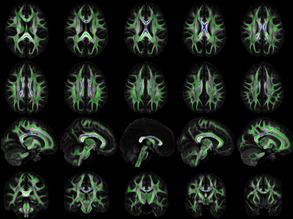

Matter of Tract

24